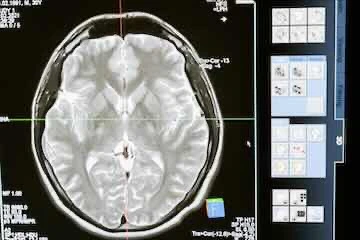

El cerebro es el centro de control del sistema nervioso central. Está compuesto por aproximadamente 86 mil millones de neuronas que se comunican a través de sinapsis, permitiendo la transmisión de señales eléctricas y químicas. El cerebro está dividido en diferentes regiones, cada una encargada de funciones específicas como el procesamiento sensorial, la regulación emocional, la memoria y el movimiento.